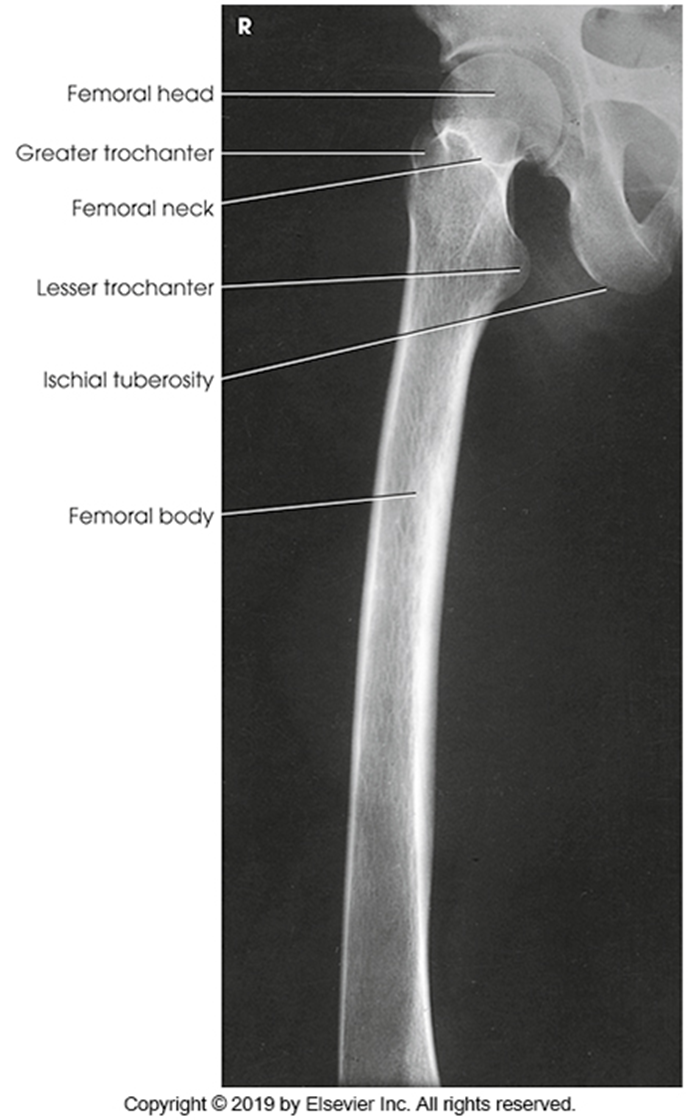

AP Femur

•Evidence of proper collimation and the presence of a side marker placed clear of the anatomy of interest

•Most of the femur and the joint nearest to the pathologic condition or site of injury (a second projection of the other joint is recommended)

•Femoral neck not foreshortened on the proximal femur

•Lesser trochanter not seen beyond the medial border of the femur or only a very small portion seen on the proximal femur

•No knee rotation on the distal femur

•Gonad shielding when indicated, but without the shield not covering proximal femur

•Any orthopedic appliance in its entirety

•Bony trabecular detail and surrounding soft tissues